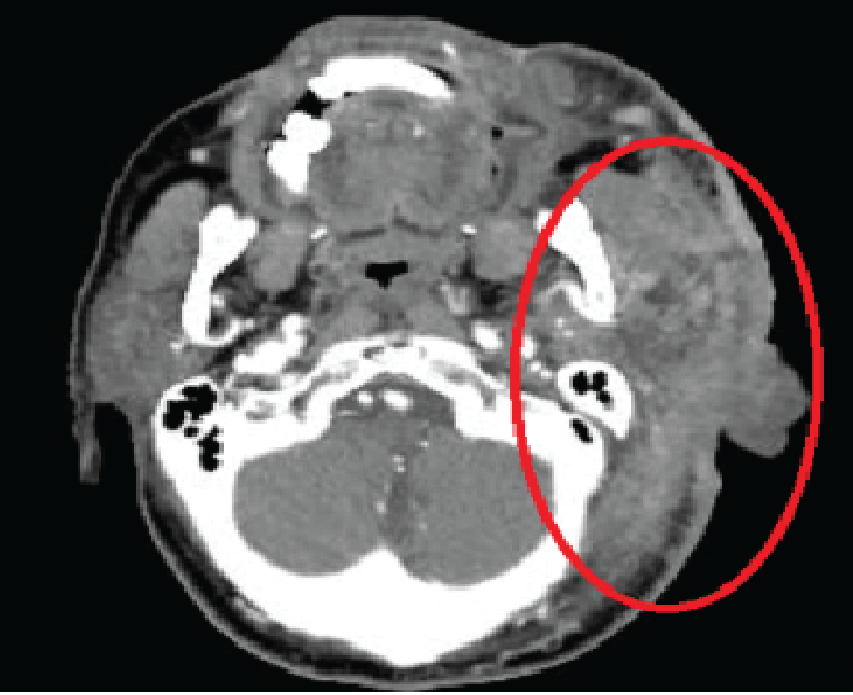

Before Treatment (Liver)

2-Month Follow-Up